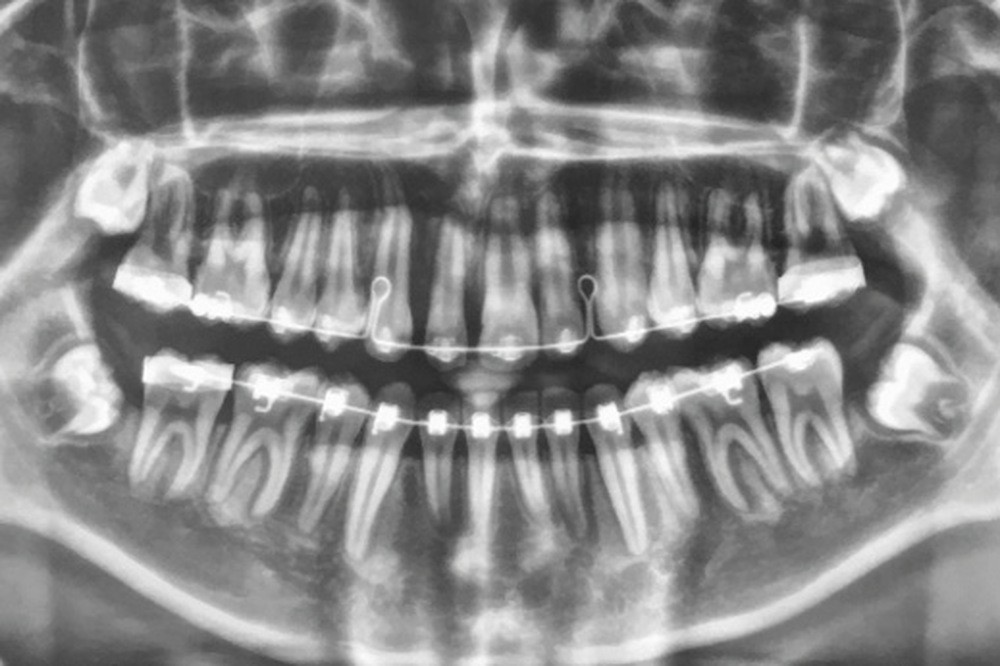

Son incisive centrale supérieure droite (11) présente un défaut de structure amélaire sévère, compromettant une technique restaurative pérenne a minima. L’examen de la panoramique (fig. 1e) et de la radiographie rétroalvéolaire de 11 (fig. 1f) objective une fracture coronaire verticale, ainsi qu’une racine grêle et courbe, peut-être en rapport avec un ancien traumatisme [1]. Le rapport couronne clinique/racine clinique est défavorable.

Lors de la phase de finitions, une séance de réévaluation radiographique des axes radiculaires (fig. 3a-b) a permis de corriger les défauts de collage et d’étudier les mouvements squelettiques et dento-squelettiques obtenus.